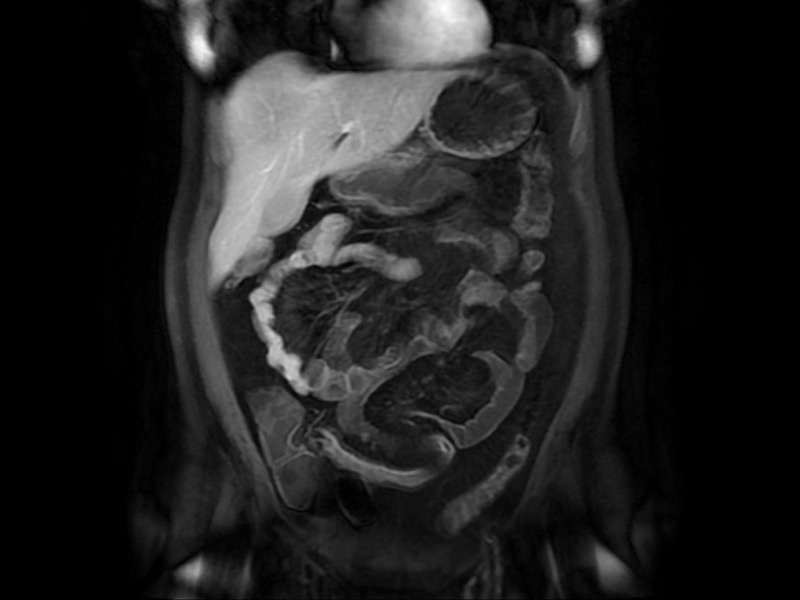

Resonancia magnética de abdomen

Es un método que se utiliza para observar el contenido y la estructura del tejido de las vísceras sólidas abdominales.

Su principal objetivo es determinar si el paciente presenta algún tipo de malformación, inflamación, quiste o tumor.

Enteroresonancia

Es el estudio del intestino delgado por medio de resonancia magnética. Permite realizar imágenes dinámicas para ver el movimiento peristáltico de las áreas intestinales e imágenes estáticas de alta resolución para evaluar la pared y los pliegues intestinales.